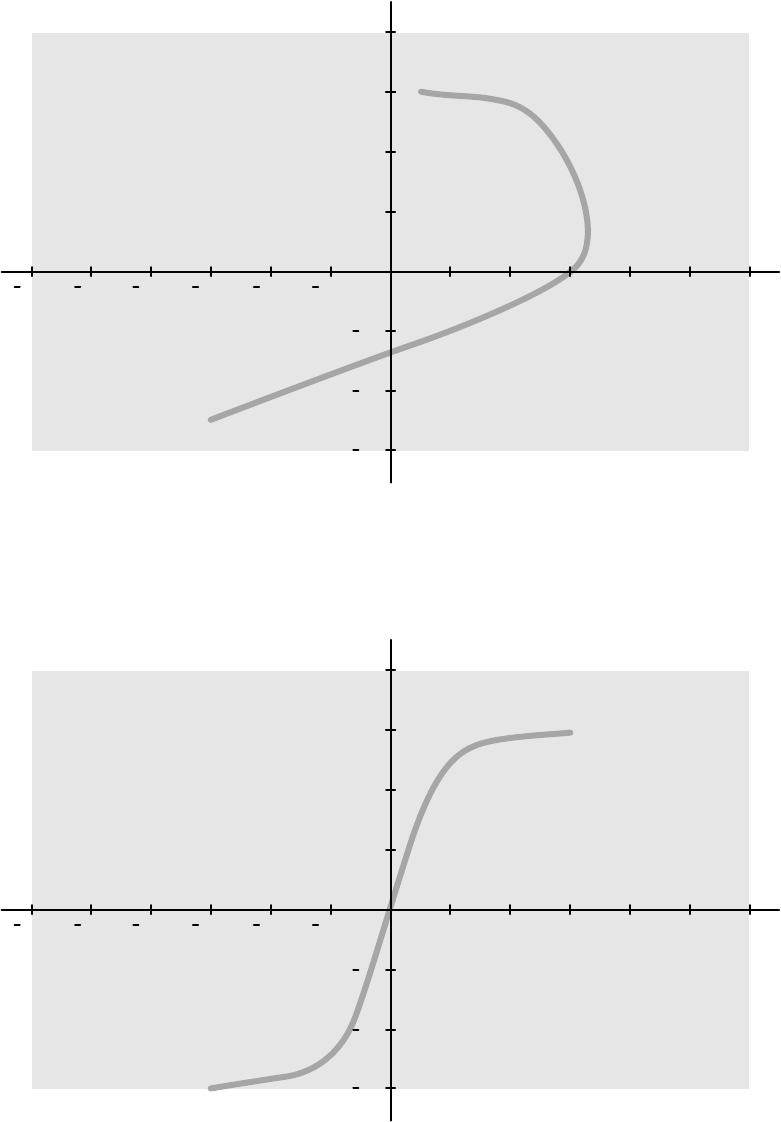

16.21.2 Mapy izokermy systemu C12/F12........................................................................ 310

16.21.3 Mapy izokermy systemu F15................................................................................ 311

16.21.4 Mapy izokermy systemu C20/F20........................................................................ 312